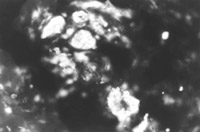

用特异的小鼠抗人角卵白19型的单克隆抗体(McAb)对正常和烧伤皮肤免疫细胞化学视察效果批注,,,,,,,,两例正常皮肤表皮再生干细胞数目较少,,,,,,,,可见少量显示荧光的表皮细胞再生干细胞(图5-4-1),,,,,,,,即角卵白19型阳性细胞。。。。 。烧伤后24h,,,,,,,,荧鲜明微镜下,,,,,,,,显示荧光的表皮再生干细胞数目中等水平(图5-4-2),,,,,,,,烧伤后4天,,,,,,,,在汗腺、毛细血管和毛囊周围可见最先增多的潜在表皮干细胞(图5-4-3)。。。。 。

图5-4-3经MEBT/MEBO治疗烧伤后4天,,,,,,,,角卵白19型阳性细胞增多  ×200

图5-4-1图5-4-7均为应用小鼠抗人角卵白19型单克隆抗体于冰冻切片染色(生物素-抗生物素卵白DSC系统间接免疫荧光)照片。。。。 。